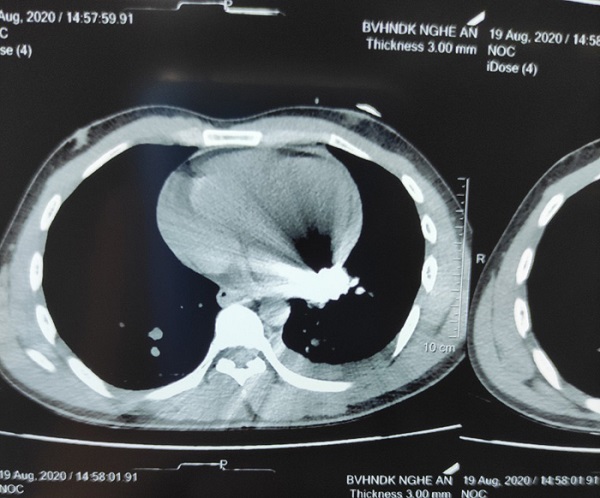

Phim cắt lớp vi tính cho thấy dị vật kim khí nằm trong tim bệnh nhân. Ảnh: suckhoedoisong.vn |

Sau khi tiếp nhận bệnh nhân, các bác sĩ tại Bệnh viện hữu nghị đa khoa Nghệ An đã tiến hành lấy máu xét nghiệm, thực hiện siêu âm phát hiện tràn dịch màng tim, dịch màng phổi trái; thực hiện chụp cắt lớp vi tính phát hiện thêm dị vật kim khí nằm trong màng ngoài tim ở thành sau tâm thất trái.